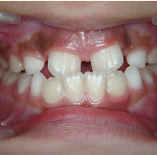

セラミック治療

こんな歯並びでもご心配なく。矯正という方法をとらなくても、ここまできれいに治せるんです。見た目だけでなく歯ブラシもやり易くなりました。笑顔に自信がつきますよ。

- 施術前

- 施術後